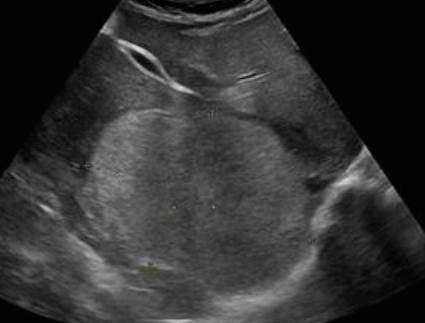

① simple cyst

US finding

- 무에코(anechoic)

- 경계가 분명하다(sharp margin)

- 후방음향증강(posterior enhancement)

- 측방음영(lateral shadow)

simple cyst ② polycystic liver disease (PLD)